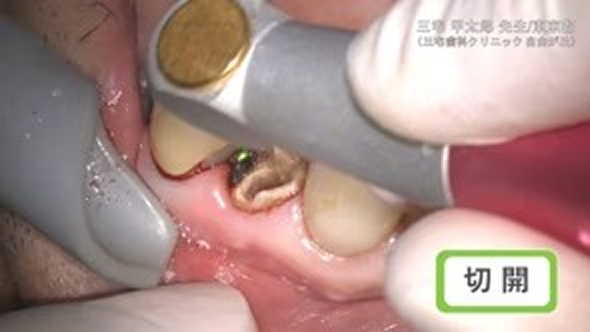

臨床例:注水型炭酸ガスレーザーNEOS(最大出力25W)を使用した先生の臨床例です。

切開